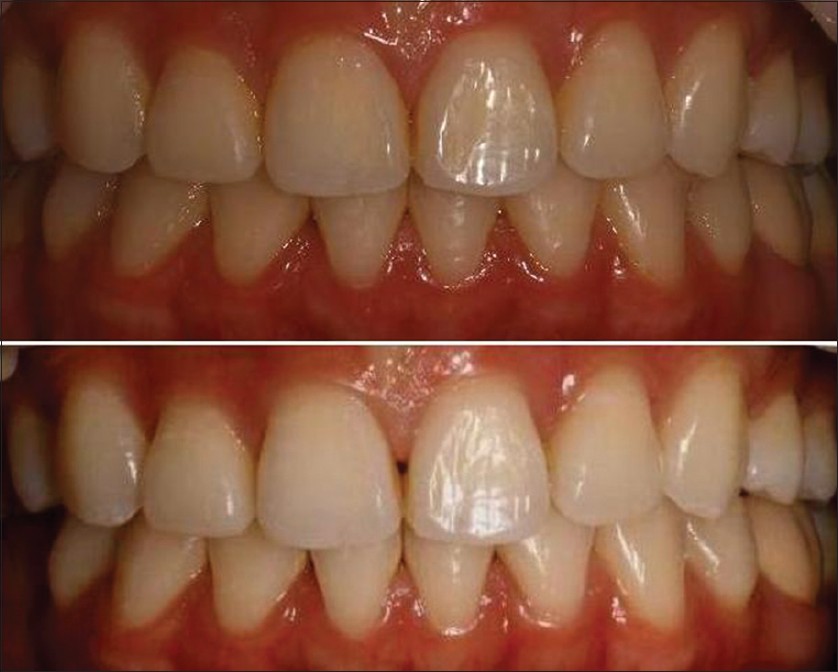

Improving smile and dental esthetics: A comprehensive periodontal and restorative approach after orthodontics |

p. 170 |

Eros Chaves, Juan Rodriguez, Maria F. S. Peres, Geoffrey Cunningham DOI:10.4103/2278-9626.134856 The esthetic demands in smile are continually rising, being thus, critical factors such as; dental midline, smile line, incisal embrasures, tooth position, width to length crown ratio, symmetry of contra-lateral gingival margins, and gingival display need to be taken into consideration. The aim of this case report is to describe the improvement of smile esthetics in a patient that after orthodontic therapy, presented excessive gingival display, asymmetric gingival margins, and shape altered upper right and left lateral incisors, which in turn compromised dental esthetics. The present clinical case required comprehensive treatment process, including proper diagnosis and excellent communication between the prosthodontist and periodontist in order to carry out successful esthetic crown lengthening and restorative dentistry. Results were followed-up for 2 years after the case completion. A pleasant smile was obtained, showing stability over time. |

| [ABSTRACT] [HTML Full text] [PDF] [Mobile Full text] [EPub] [Citations (3) ] [Sword Plugin for Repository]Beta |